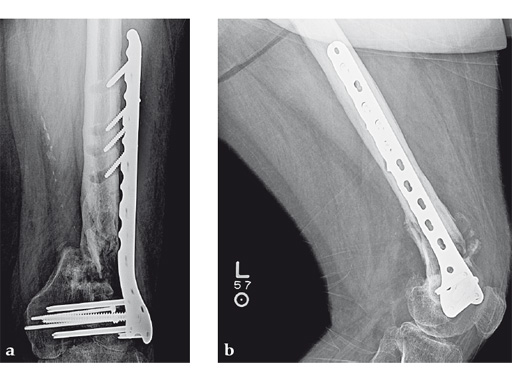

Case 2: A 69-year-old man following revision total knee arthroplasty with a megaprosthesis, requiring an osteotomy of his femoral shaft for realignment of his femoral component. The patient developed a nonunion of his osteotomy and subsequently fractured the stem of his megaprosthesis.

Surgical treatment of this nonunion consisted of compression plating using the VA-LCP Curved Condylar Plate. The arthroplasty components were stable. The proximal piece of the stem was extremely well fixed. Variable-angle locked screws were targeted between his femoral shell and stem in the distal segment allowing excellent distal fixation such that an articulated tensioning device could be attached proximally and the nonunion could be compressed and the alignment improved.